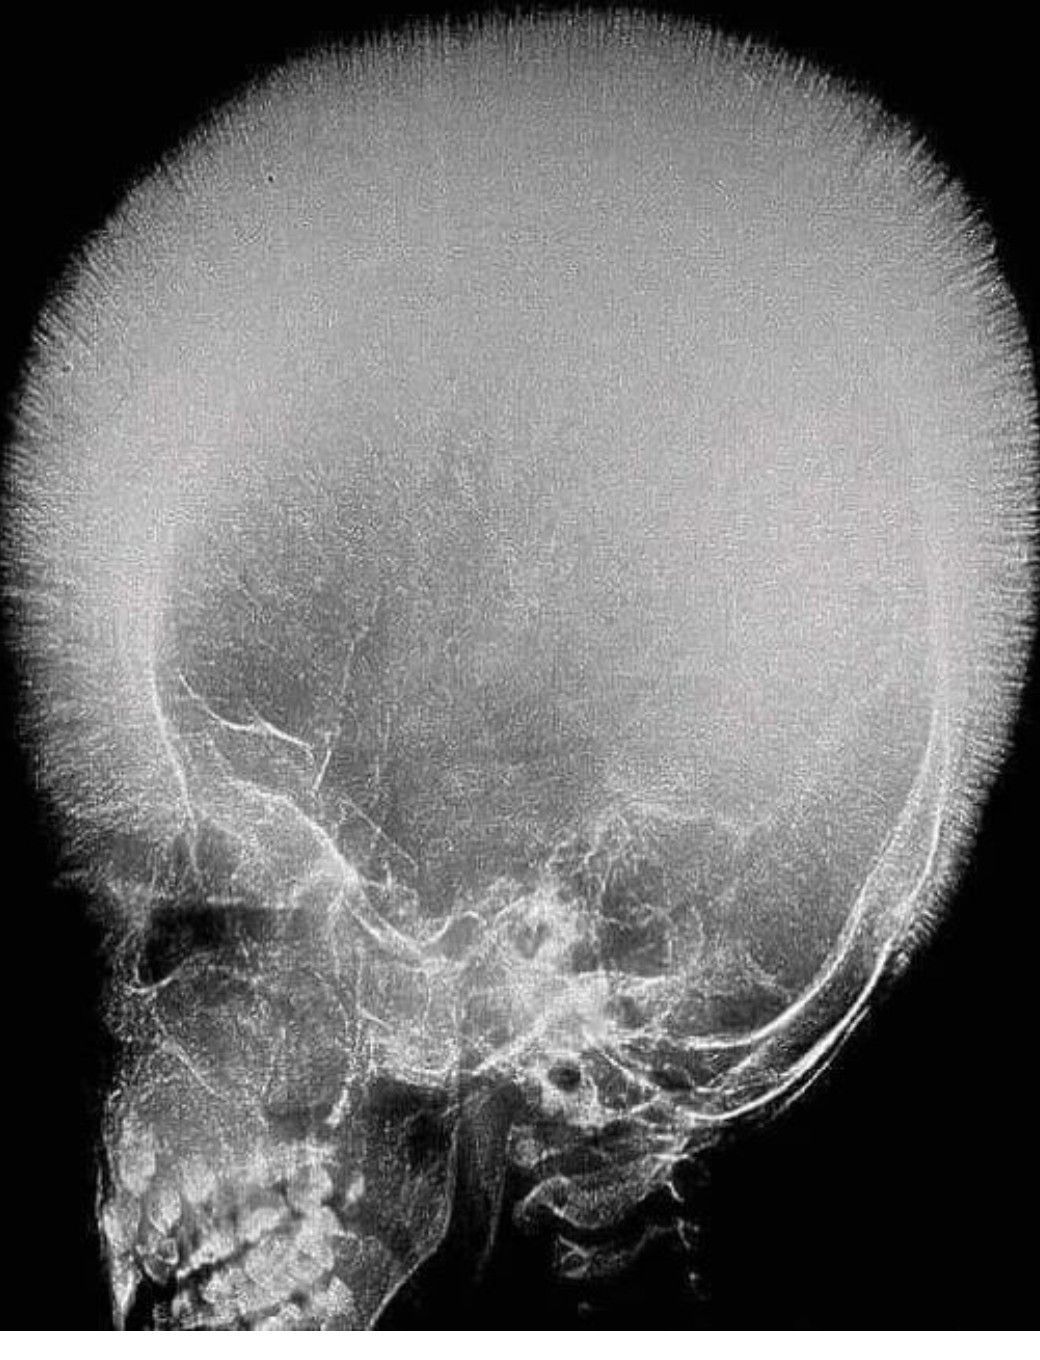

Identify the Appearance

Identify the appearance in the skull radiograph above.